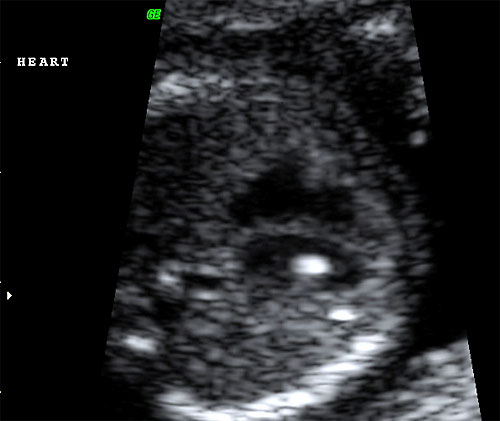

- Echogenic intracardiac foci

- Detection of Aneuploidy: "Soft Signs"

- All are more prevalent in aneuploid fetus